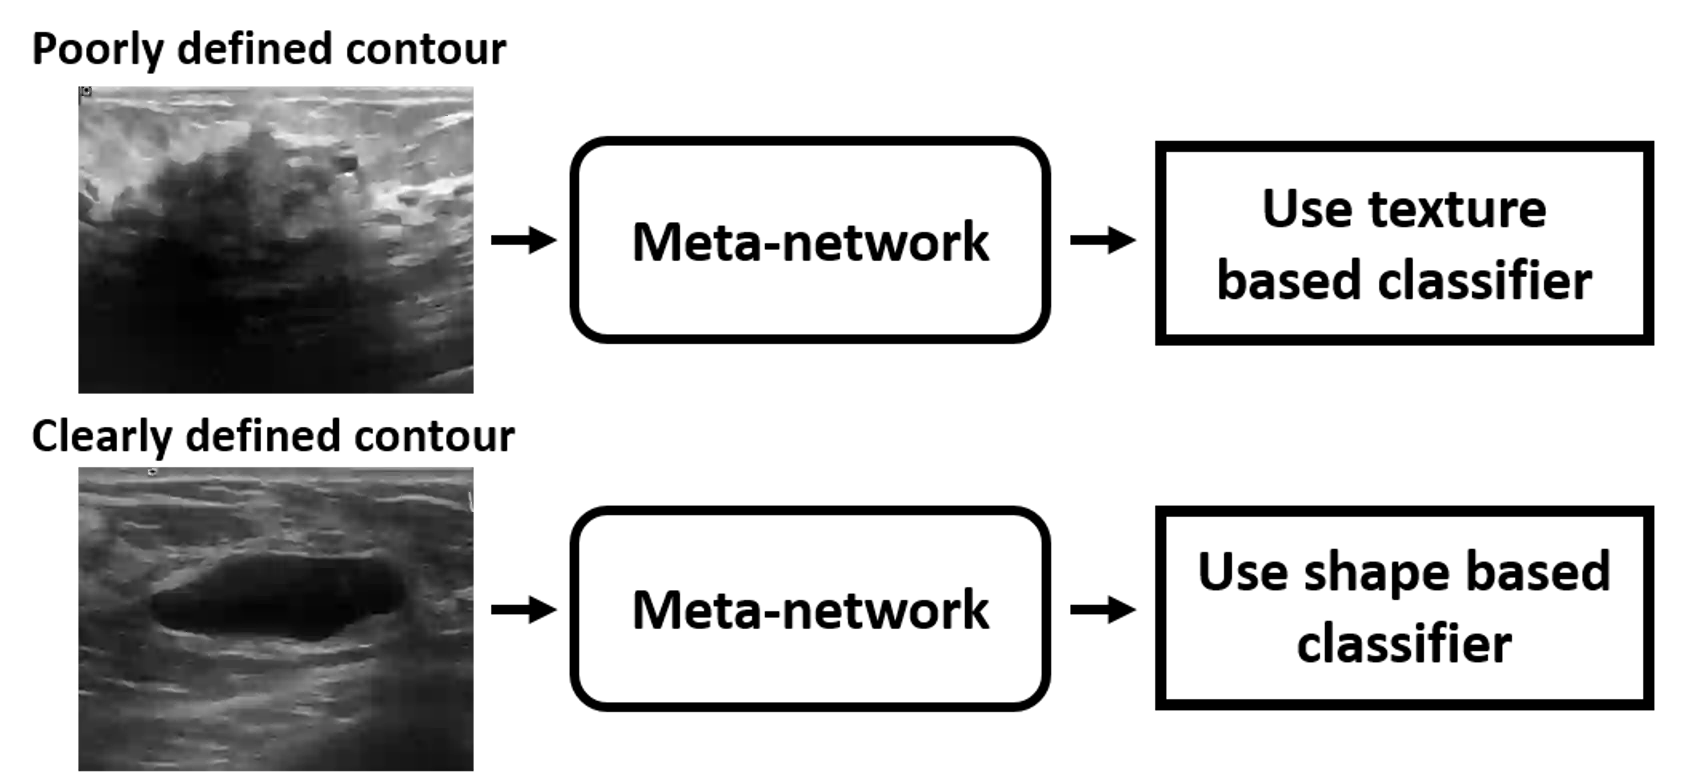

Standard classification methods based on handcrafted morphological and texture features have achieved good performance in breast mass differentiation in ultrasound (US). In comparison to deep neural networks, commonly perceived as "black-box" models, classical techniques are based on features that have well-understood medical and physical interpretation. However, classifiers based on morphological features commonly underperform in the presence of the shadowing artifact and ill-defined mass borders, while texture based classifiers may fail when the US image is too noisy. Therefore, in practice it would be beneficial to select the classification method based on the appearance of the particular US image. In this work, we develop a deep meta-network that can automatically process input breast mass US images and recommend whether to apply the shape or texture based classifier for the breast mass differentiation. Our preliminary results demonstrate that meta-learning techniques can be used to improve the performance of the standard classifiers based on handcrafted features. With the proposed meta-learning based approach, we achieved the area under the receiver operating characteristic curve of 0.95 and accuracy of 0.91.